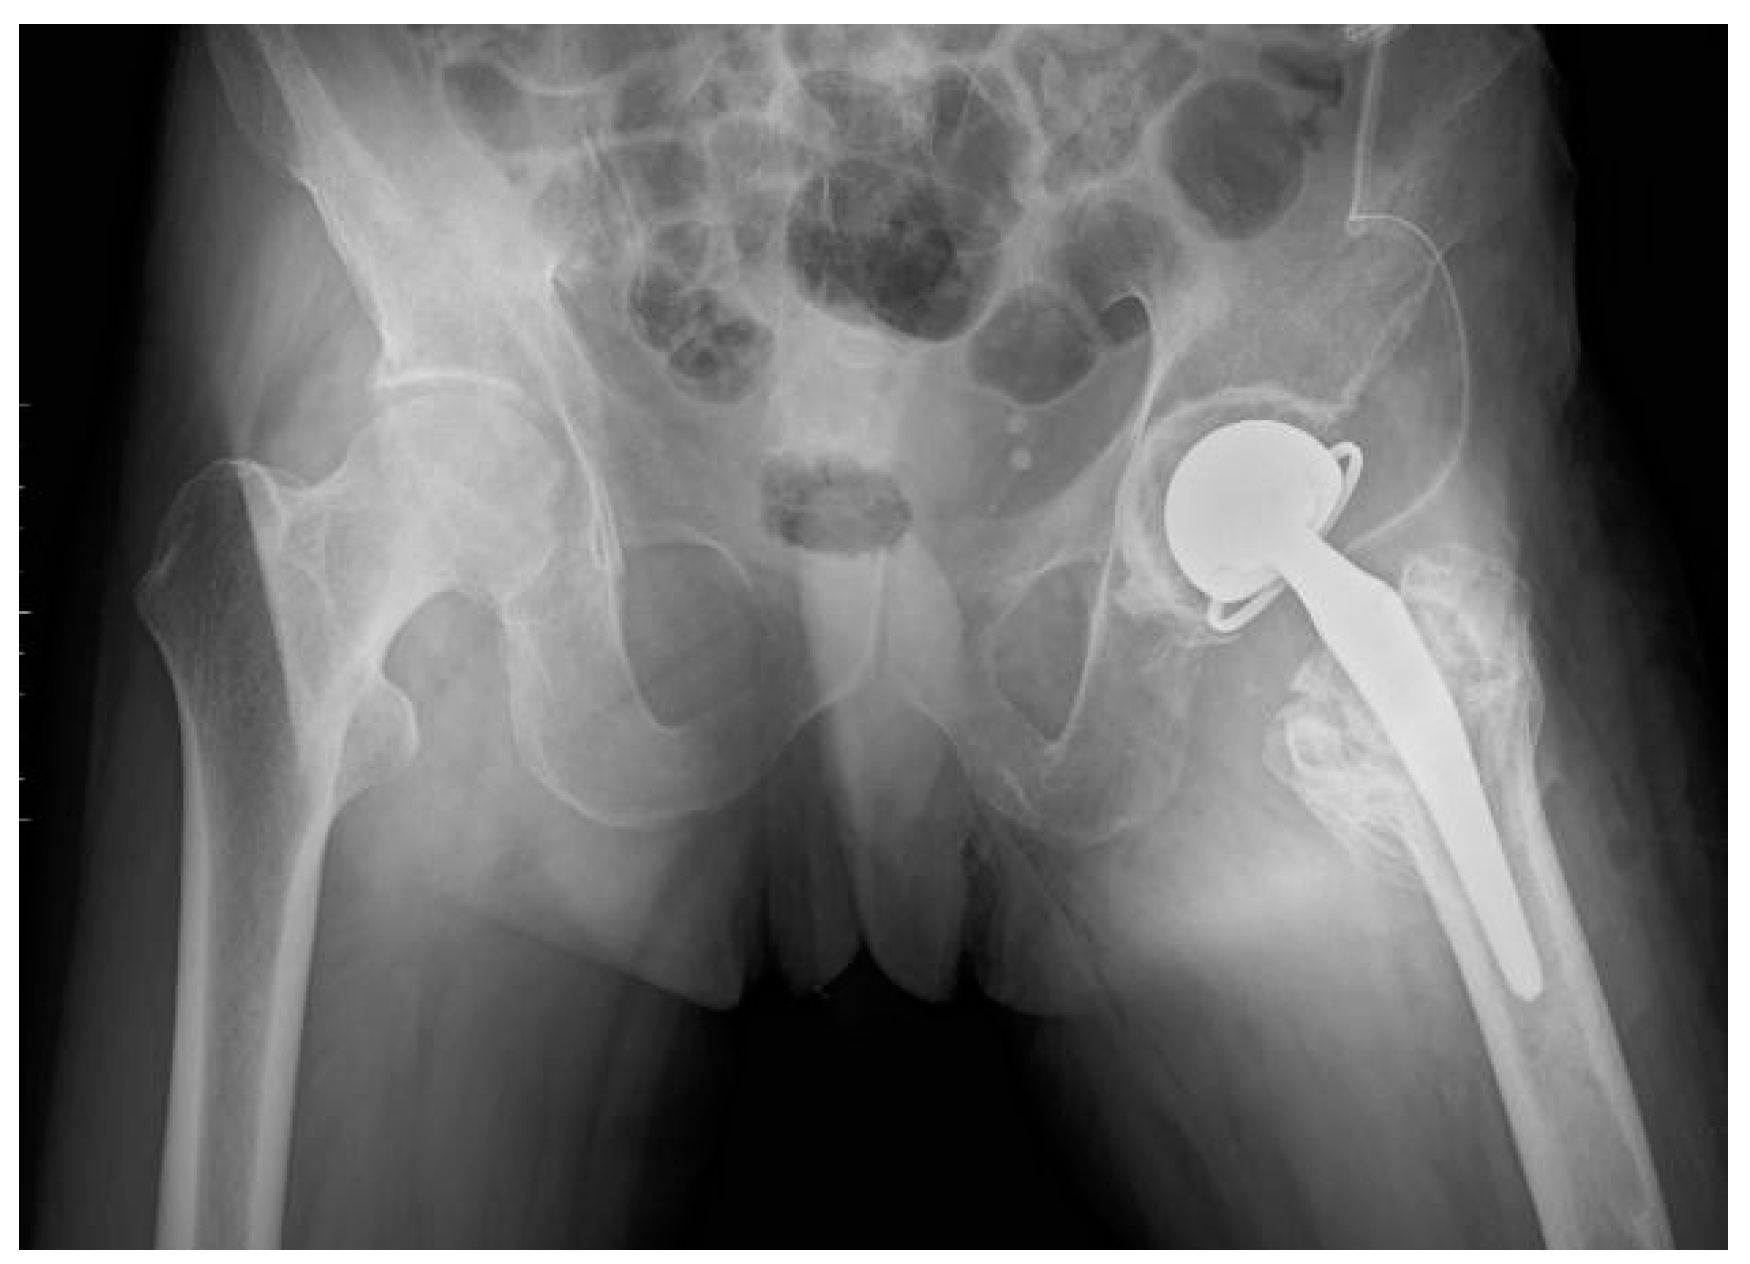

| Third Stage of Treatment—October 2023 Snap-on Prosthesoplasty with Adductor Tenotomy | ||

2.5. Treatment